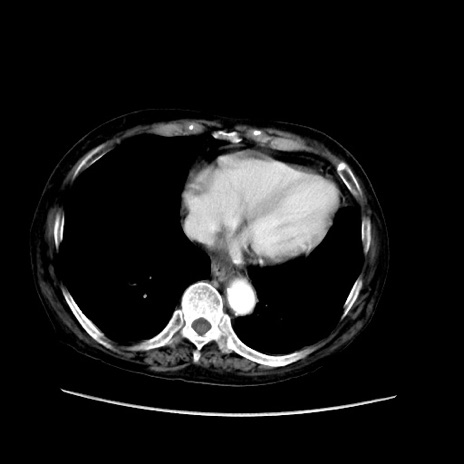

症例31(横断像)

【症例】80歳代 女性

【主訴】腹部膨満感

【現病歴】他院にて肝硬変にてフォロー中。1週間前から便秘、腹部膨満感、臍部腫瘤あり受診となる。

【既往歴】肝硬変

【身体所見】腹部膨隆あり、皮膚変化なし、疼痛なし。

【データ】WBC 4600、CRP 0.25